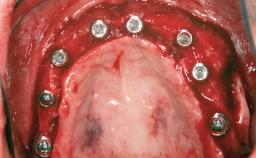

# of Implants 8

Bone Augmentation Horizontal|Sinus Floor Elevation|Staged|Vertical

Augmentation Materials Autogenous chips|Autogenous block(s)